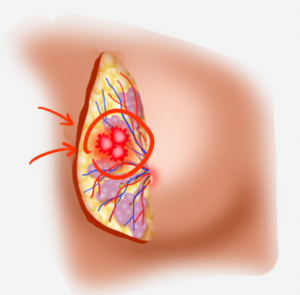

Breast nodules typically refer to lumps or masses found in the breast. Most of these nodules are benign (non-cancerous). Some common benign causes include breast infections, fibroadenomas, simple cysts, fat necrosis, fibrocystic changes, and intraductal papillomas.

However, a small percentage of breast nodules can be malignant (cancerous), and they may exhibit the following warning signs:

- Size: Larger nodules tend to raise concerns more easily.

- Shape: Nodules with irregular or jagged edges have a higher likelihood of malignancy.

- Texture: If a nodule feels hard or has an uneven texture upon touch, further investigation is needed. This is especially important for women over 50 years old, as the risk of malignancy increases with age.